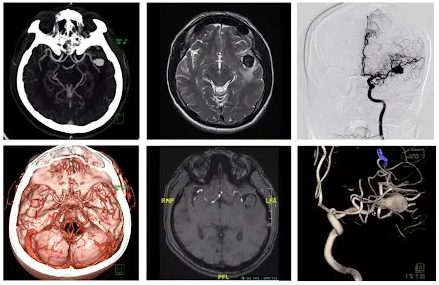

Tumor Removals: Neurosurgeons often perform procedures to remove brain tumors, which require a high degree of precision and care to minimize damage to healthy tissue. 3D-printed models allow surgeons to study the tumor's location, size, and relationship to surrounding structures before the actual surgery. Surgeons can practice different approaches and techniques to plan the optimal path for tumor removal.

Aneurysm Clippings: Aneurysms are weakened and bulging areas in blood vessels that can rupture and cause life-threatening bleeding. Neurosurgeons use 3D-printed models to simulate the delicate procedure of clipping aneurysms. These models help surgeons determine the most effective clip placement to isolate the aneurysm while preserving nearby blood vessels and neural structures.